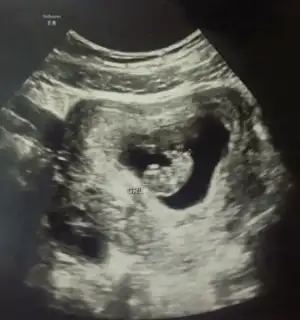

Ben şunu anlamadım ultrason kağıdını elime alınca bebegim bariz solda bu kesin.. Ama doktor ultrason u hep sagıma koyup bakıyor yani aslında bebek sağda ultrasonda direk bakınca da sağda.. Şimdi kağıda göremi yoksa ultrason a göremi yorum yapcaz

İşte fark orda cnm karından Usg de öyle oluyor,vajinal da sağdaysa sağda soldaysa solda.usg kağıdın elindeyse yorum yapayım ben o yüzden usg karındansa veya vajinalsa diye yorum yapiyorum

Canim kağıdı elime alıp bakınca kese solda duruyor . Bu görüntü ters görüntü mu yani kağıda bakınca solda ama karında kese sağda mi oluyo